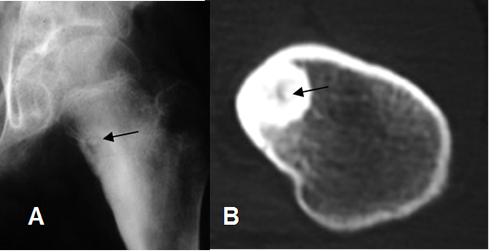

Fig 60. Osteoma osteoide.

A: Rx AP y B: TAC axial. Imagen cortical y esclerótica, pudiendo identificar el nido parcialmente calcificado.